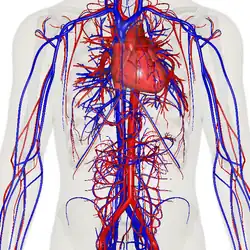

The human circulatory system (simplified). Red indicates oxygenated blood carried in arteries. Blue indicates deoxygenated blood carried in veins. Capillaries join the arteries and veins.